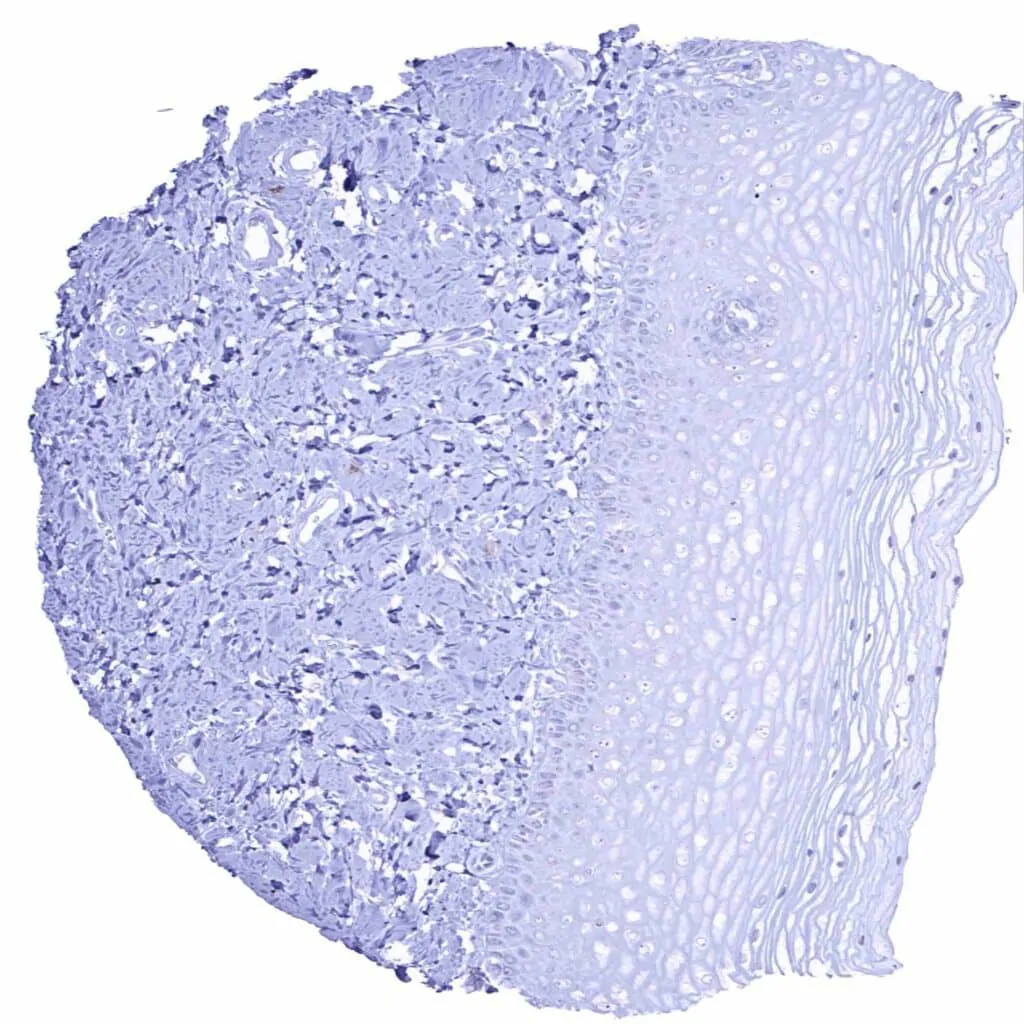

Urinary bladder, urothelium – Urothelial cells are CD38 negative. Some inflammatory cells show distinct staining